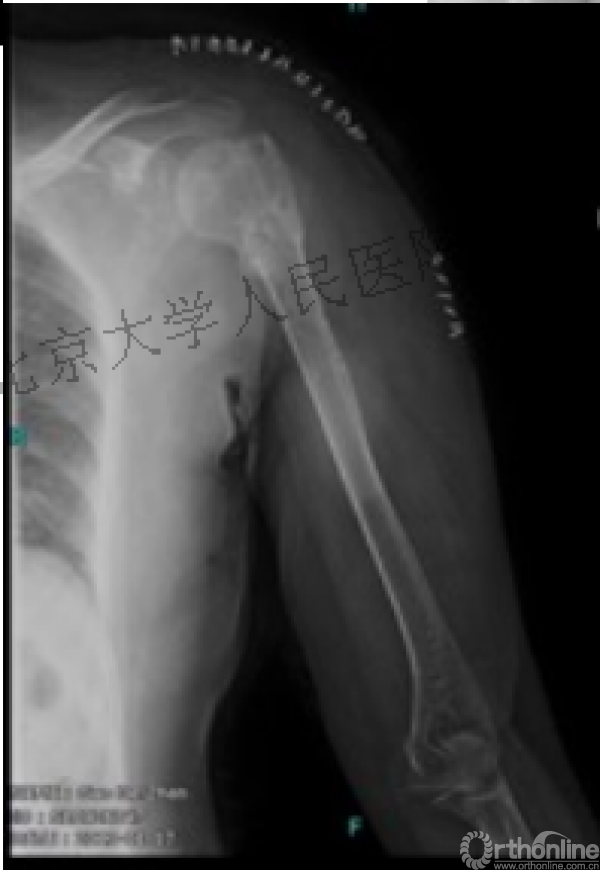

另一个留有遗憾的病例,您的选择?PHN?

临床中的广泛内固定治疗不断地提出思考